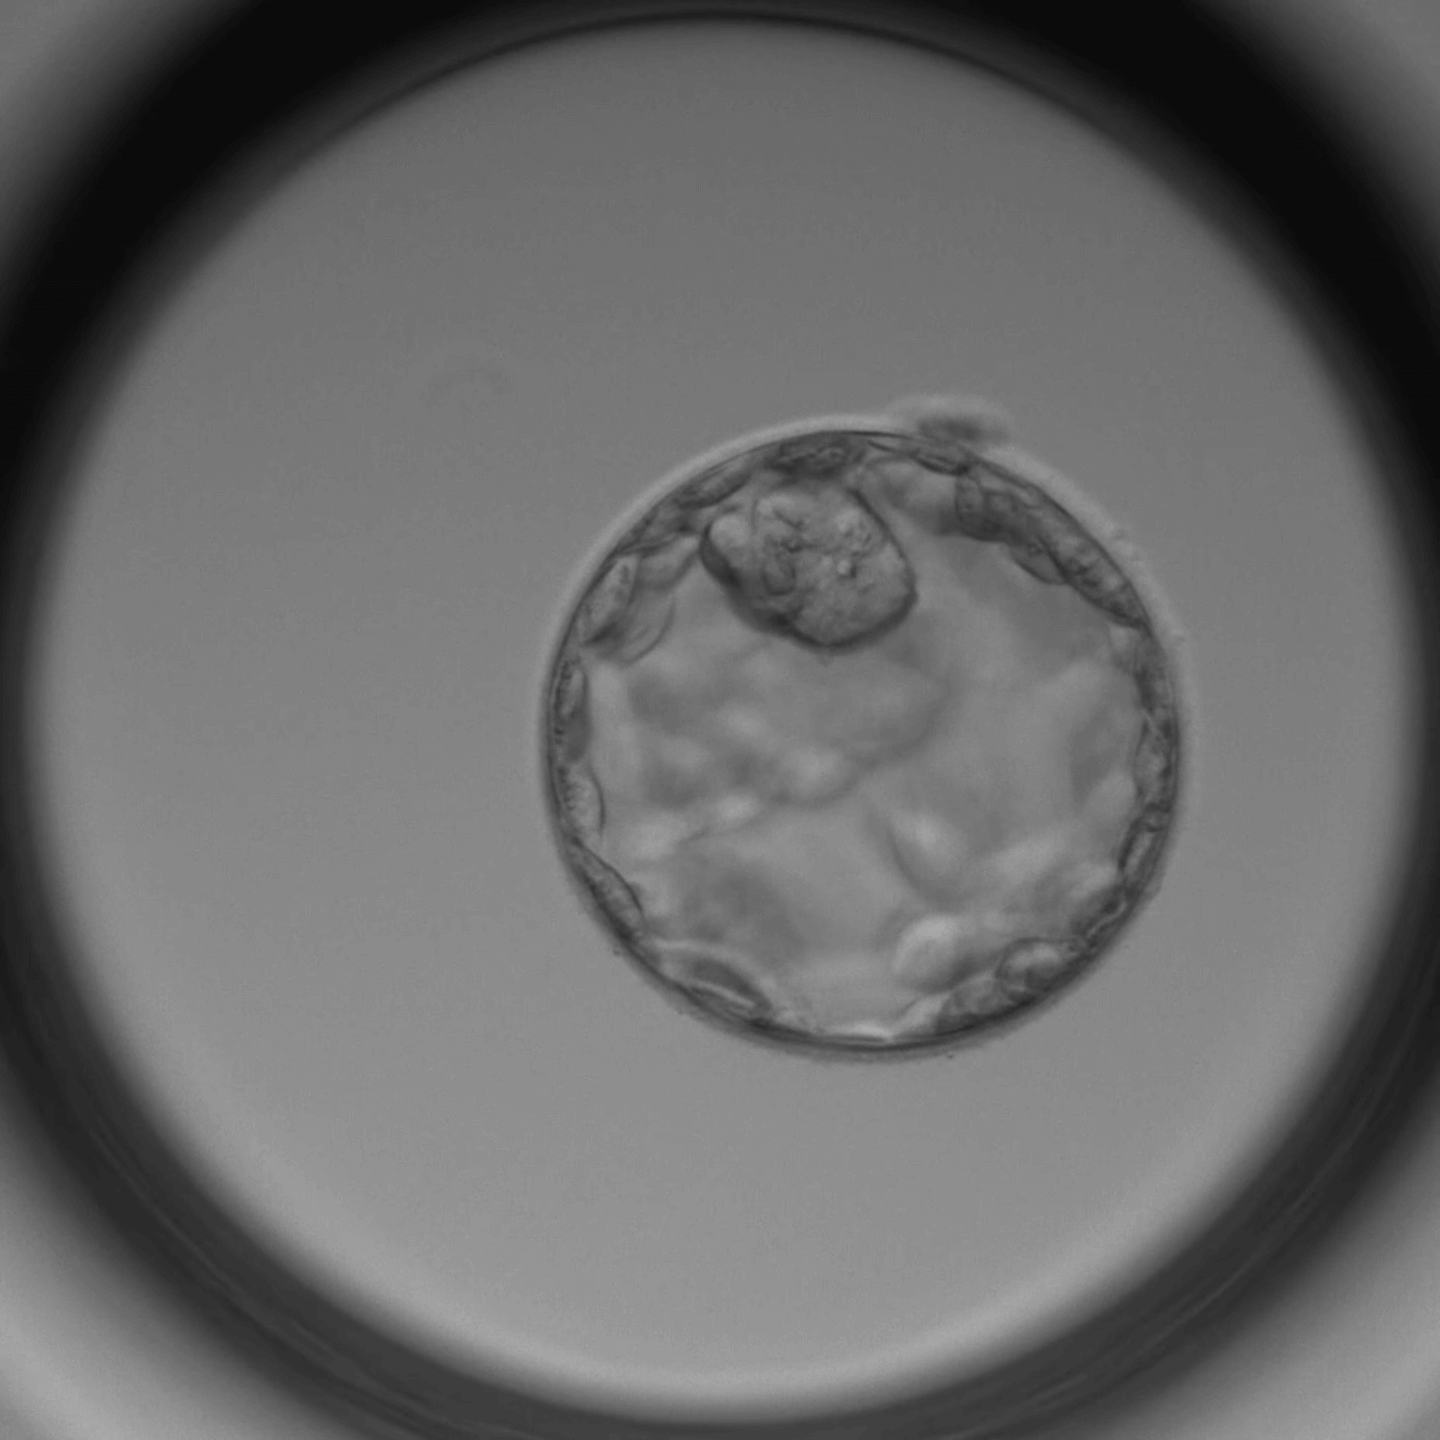

Ein Timelapse-Inkubator ermöglicht die kontinuierliche Überwachung der Embryonen durch eine Kamera, während herkömmliche Inkubatoren Embryonen regelmäßig zur Untersuchung entnommen werden müssen.

Nein, die Kamera im Timelapse-Inkubator arbeitet kontaktlos und beeinträchtigt die Entwicklung der Embryonen nicht. Sie ermöglicht eine schonende Überwachung.

Ja, unsere Klinik bietet den Patienten die Möglichkeit, die Timelapse-Bilder ihrer Embryonen zu sehen und den Entwicklungsprozess zu verfolgen.

Der Einsatz eines Timelapse-Inkubators kan die Erfolgschancen erhöhen, indem er eine genauere Auswahl der besten Embryonen ermöglicht und stabile Kulturbedingungen gewährleistet.